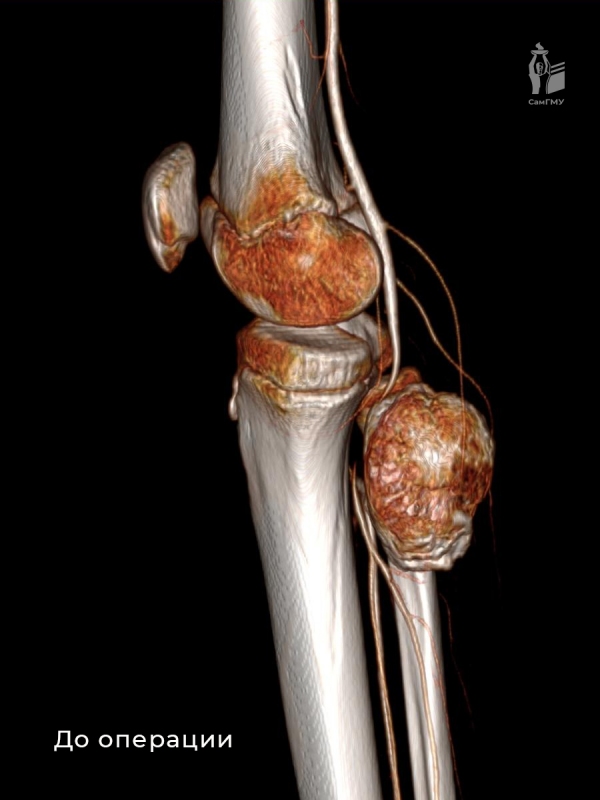

Сложность операции заключалась в необходимости сохранения всех функционально важных элементов. Для выполнения этой трудоёмкой задачи была сформирована мультидисциплинарная команда, которая включала детского сосудистого хирурга Николая Свечкова из Самарского областного клинического кардиологического диспансера. После проведения тщательной диагностики, включая КТ-ангиографию, врачи провели оперативное удаление нароста. Хирурги аккуратно отделили образование от малоберцовой кости и мягких тканей, освободив подколенную артерию без нанесения повреждений.